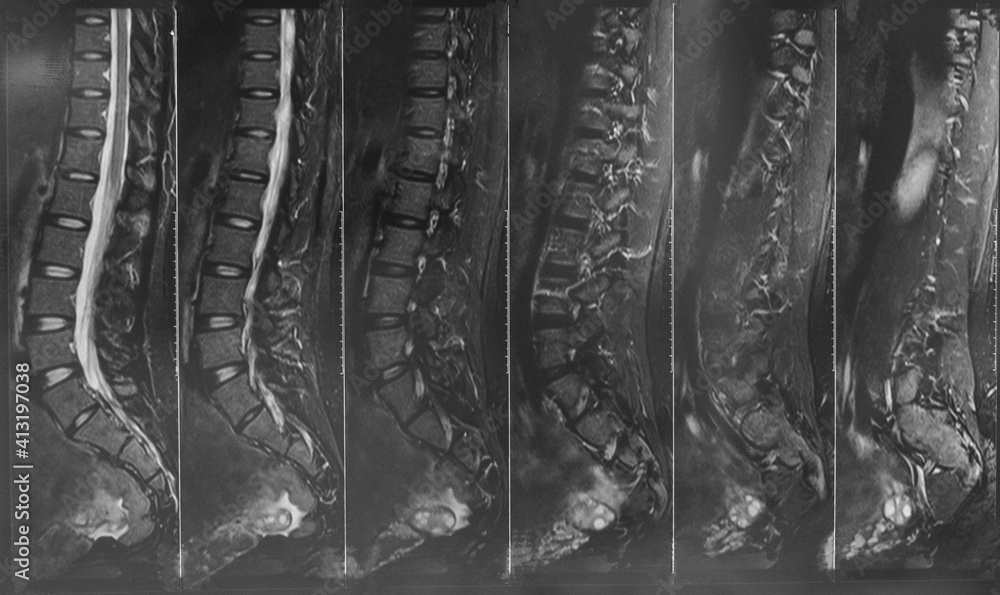

From stock.adobe.com

X ray MRI of lumbosacral spine (LS spine) case of low back pain Chronic Back Pain Normal X Ray the evaluation for low back pain should include a complete, focused medical history looking for red flags, which include, but are not limited. low back pain is the second most common complaint in the united states, with a lifetime incidence of 80% to 85%. Information about spinal alignment can be obtained under static and. Patients who continue to. Chronic Back Pain Normal X Ray.